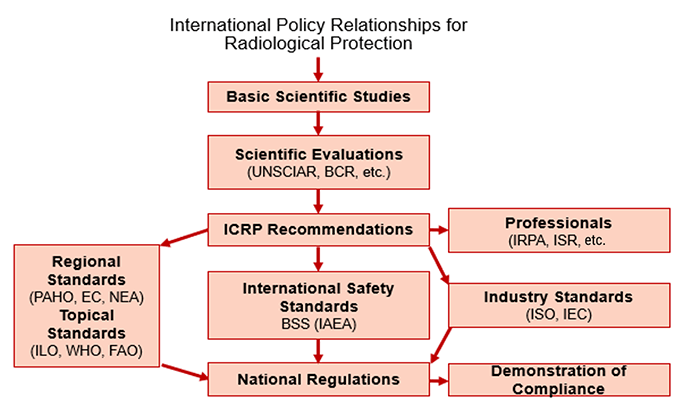

The National Council on Radiation Protection (NCRP) was established to support radiation protection by providing independent scientific analysis, information, and recommendations that represent the consensus of leading scientists.

The International Commission on Radiological Protection (ICRP) is an independent, international, non-governmental organization, whose mission is to provide recommendations and guidance on radiological protection concerning ionizing radiation.